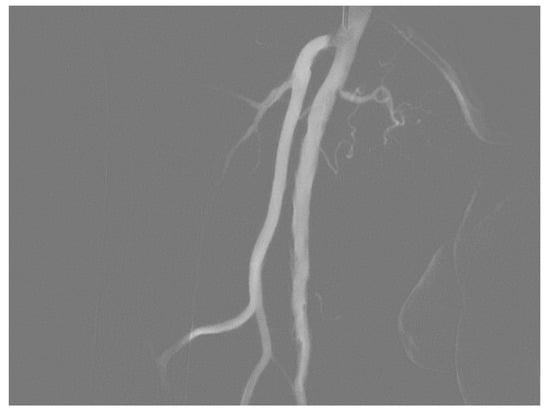

3. Angiographic Findings

3.1. Stenosis and Occlusion